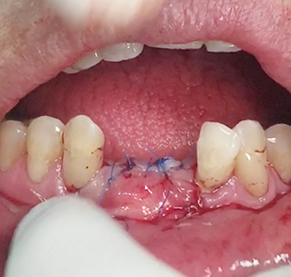

Implants/Bone Grafting

Simultaneous bone graft and implant placement